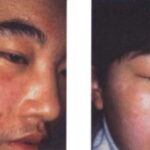

VOGT-KOYANAGI-HARADA SYNDROME

The Vogt-Koyanagi-Harada syndrome (VKH) consists of vitiligo in association with uveitis, aseptic meningitis, dysacusis, tinnitus, poliosis, and alopecia. It is a rare, systemic, T-cell-mediated autoimmune disorder. VKH syndrome is associated with other autoimmune disorders such as autoimmune polyglandular syndrome, hypothyroidism, Hashimoto thyroiditis, and diabetes mellitus. VKH syndrome classically occurs in three phases. During the first phase, the meningoencephalic phase, patients may have headache, meningismus, seizures, muscle weakness, or paralysis after a prodrome of fever, malaise, nausea and vomiting. Subsequently, the acute ophthalmic phase occurs when patients may develop photophobia, eye pain, and altered visual acuity. Patients may develop uveitis, iridocyclitis, choroiditis, and retinal detachment during this phase and can later develop complications such as cataracts and glaucoma. Vitiligo, alopecia, and poliosis22 usually follow, but can occur before the other manifestations.

ALEZZANDRINI SYNDROME

The constellation of clinical findings in Alezzandrini syndrome includes facial vitiligo, poliosis, deafness, and unilateral tapetoretinal degeneration. The etiology remains poorly understood, but as in vitiligo and VKH syndrome, autoimmune processes are thought to be involved. Only a few cases have been reported since the first description of a patient with vitiligo, poliosis, and unilateral retinitis in 1959.23